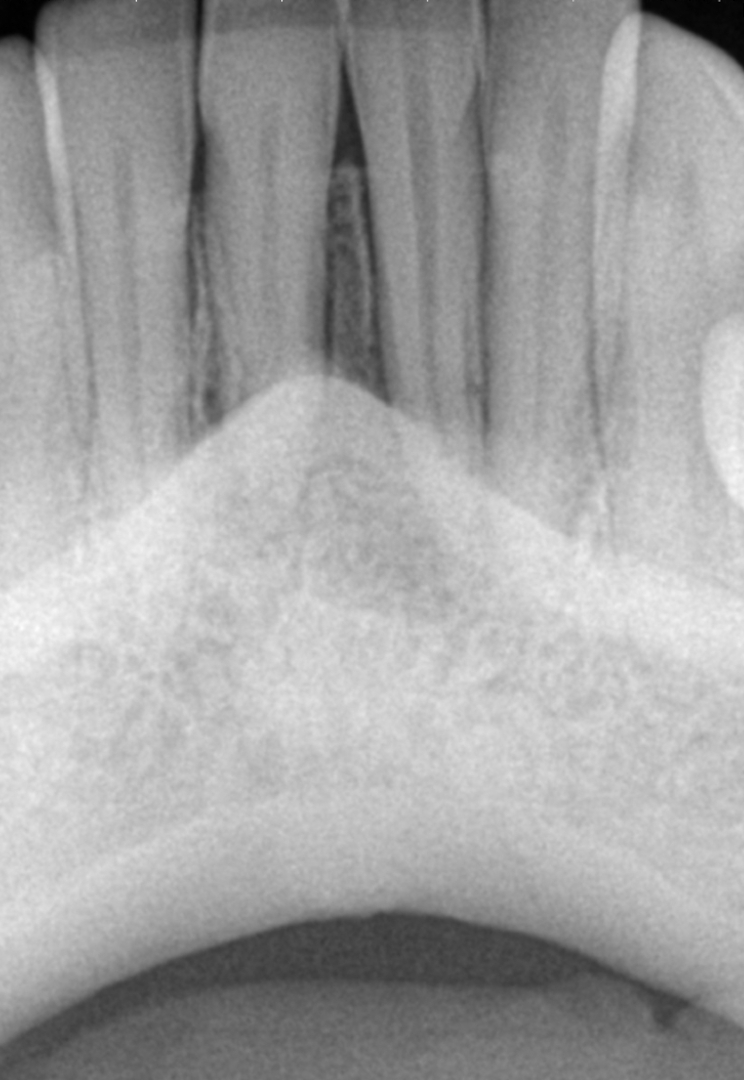

A young female patient, a model who cared a great deal about her appearance and wished to keep it natural-looking, came to our office with a swelling of her lower jaw under the two central incisors. Upon consulting with our periodontist and prosthodontist, a pocket of over 20 mm width, going from one central incisor to the other, was discovered, indicating that the entire cortical plate was gone. This, along with the Class III mobility of both central incisors, was a red flag to the periodontist. In vitality testing of the teeth, the two central incisors did not respond to a cold test and the remaining teeth were normal. On the radiograph, the problem was not visible (Fig. 1). An i-CAT scan was taken to gain a better understanding of the problem. The scan showed a horizontal and a vertical view of the lesion. The horizontal view showed loss of both the cortical and trabecular bone from the left central incisor to the right lateral incisor, with a total length of almost 14.11 mm and a depth of 6.28 mm (Fig. 2a). The vertical views showed that there was no bone on the buccal aspect and no bone under the central incisors almost to the level of the apex (Figs. 2b & c). There was horizontal bone loss of 5.5 mm to 6.3 mm. This was a situation often considered hopeless, and saving these teeth seemed impossible.

Figs. 2a–c: Horizontal view of the i-CAT scan showing a large bone defect (a). Vertical views of both central incisors showing the bone loss (b & c).